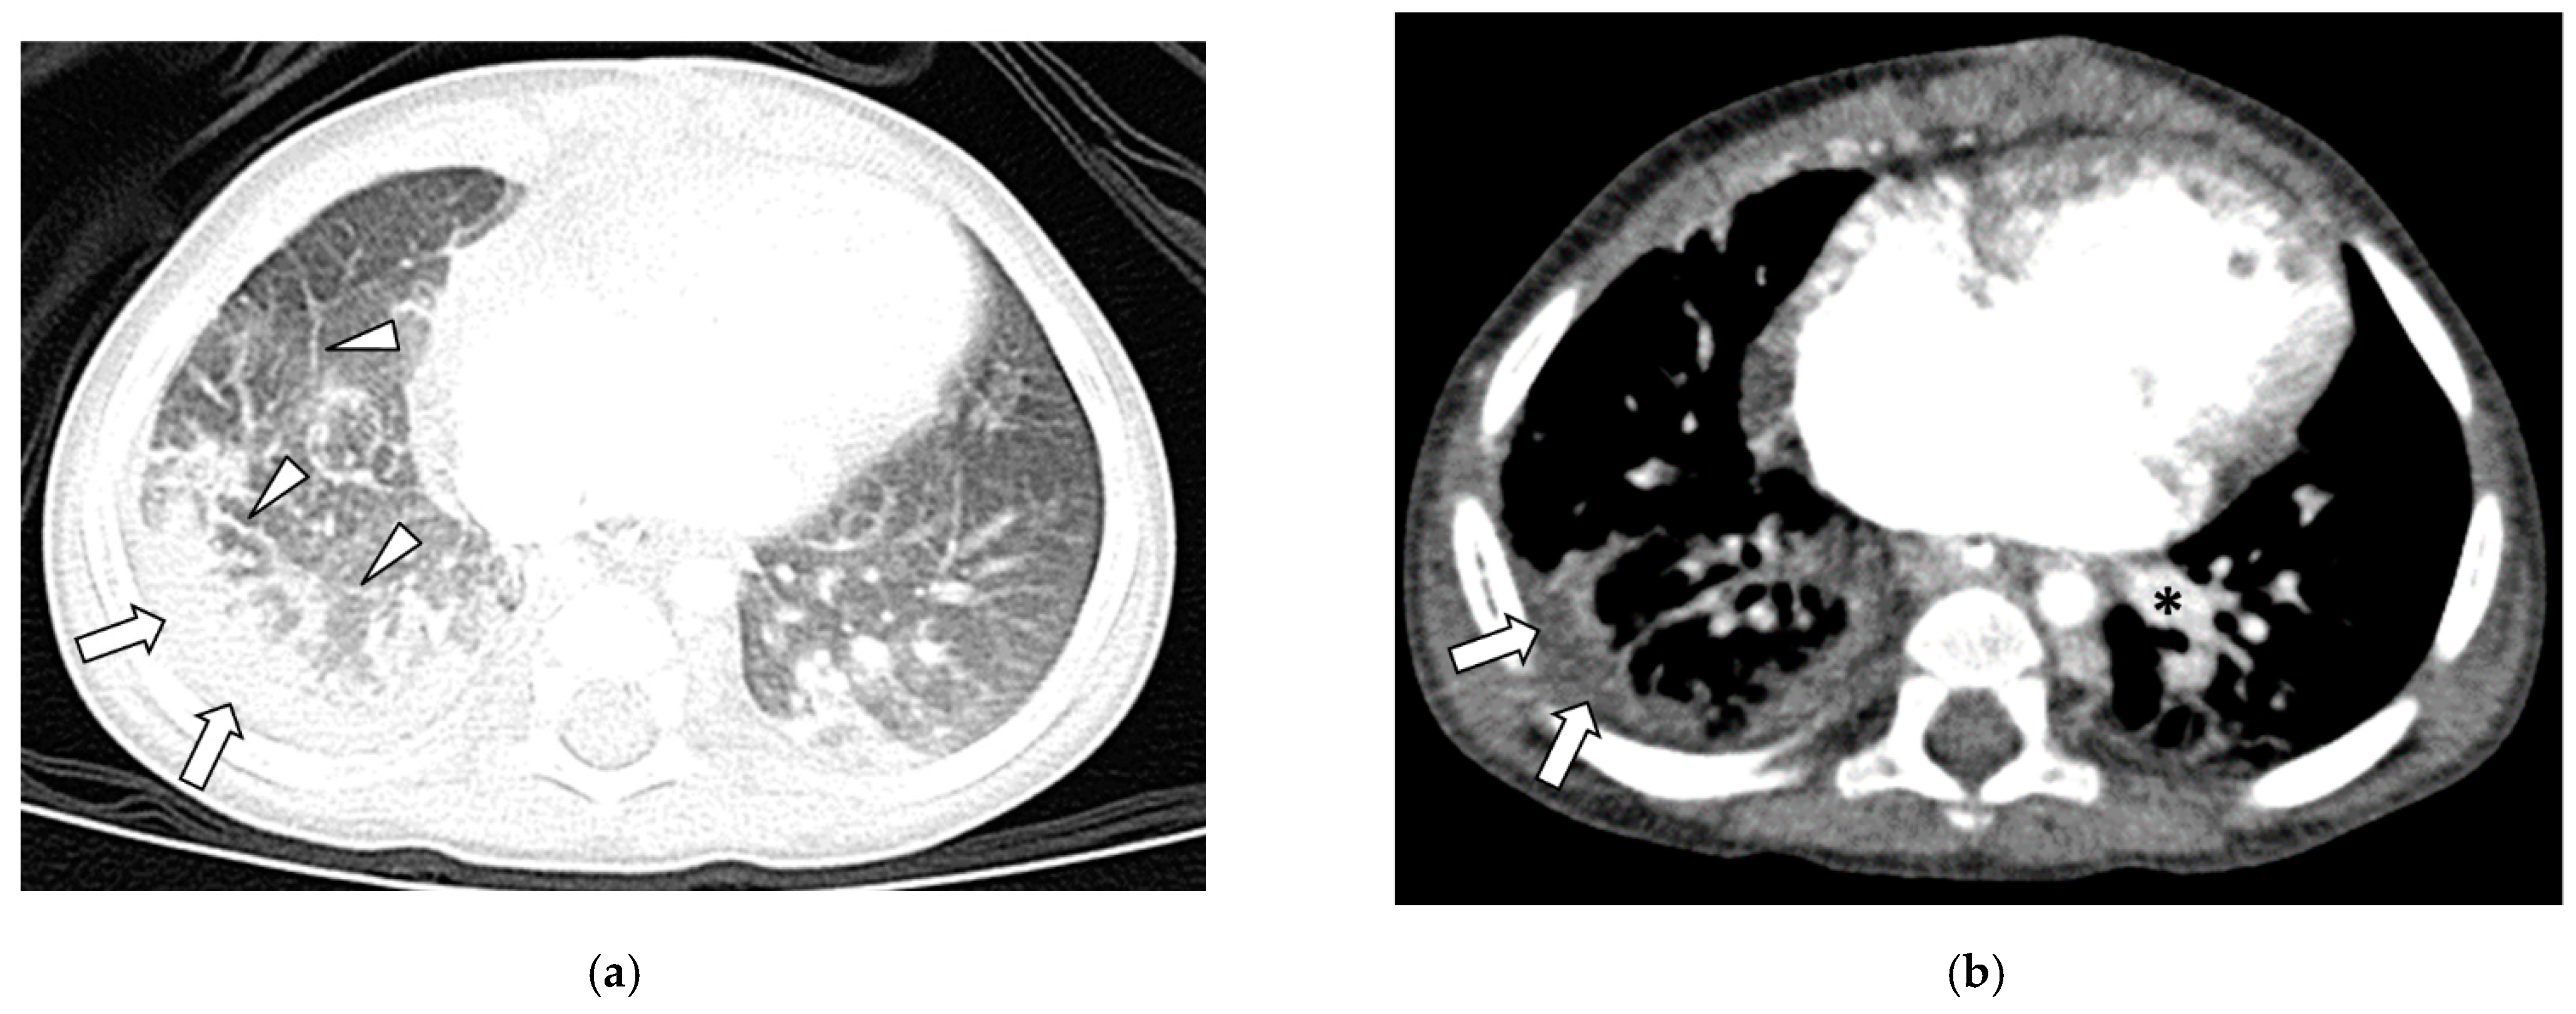

3.2. Thoracic MDCT Findings

3.3. Lung Findings

3.5. Pleural Findings

- Lee, E.; Callahan, R.; Vargas, S.; Jenkins, K.; Park, H.; Gauthier, Z.; Winant, A. Extravascular MDCT Findings of Pulmonary Vein Stenosis in Children with Cardiac Septal Defect. Children 2021, 8, 667. [Google Scholar] [CrossRef]

- Lee, E.Y.; Jenkins, K.J.; Vargas, S.O.; Callahan, R.; Park, H.J.; Gauthier, Z.; Winant, A.J. Thoracic multidetector computed tomography angiography of primary pulmonary vein stenosis in children: Evaluation of characteristic extravascular findings. J. Thorac. Imaging 2021, 36, 318–325. [Google Scholar] [CrossRef] [PubMed]

- Lee, E.Y.; Vargas, S.O.; Jenkins, K.J.; Callahan, R.; Park, H.J.; Gauthier, Z.; Winant, A.J. Secondary Pulmonary Vein Stenosis Due to Total Anomalous Pulmonary Venous Connection Repair in Children: Extravascular MDCT Findings. Children 2021, 8, 726. [Google Scholar] [CrossRef] [PubMed]